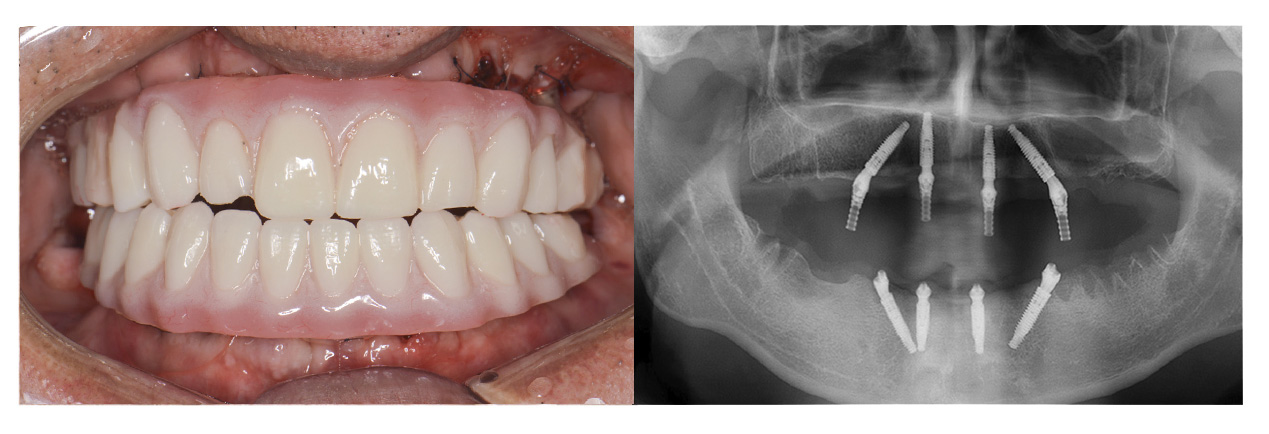

症例②オールオン4

• Before

• After

咀嚼、審美障害。歯周病でグラグラな歯を全部抜歯してオールオン4で治療した症例。